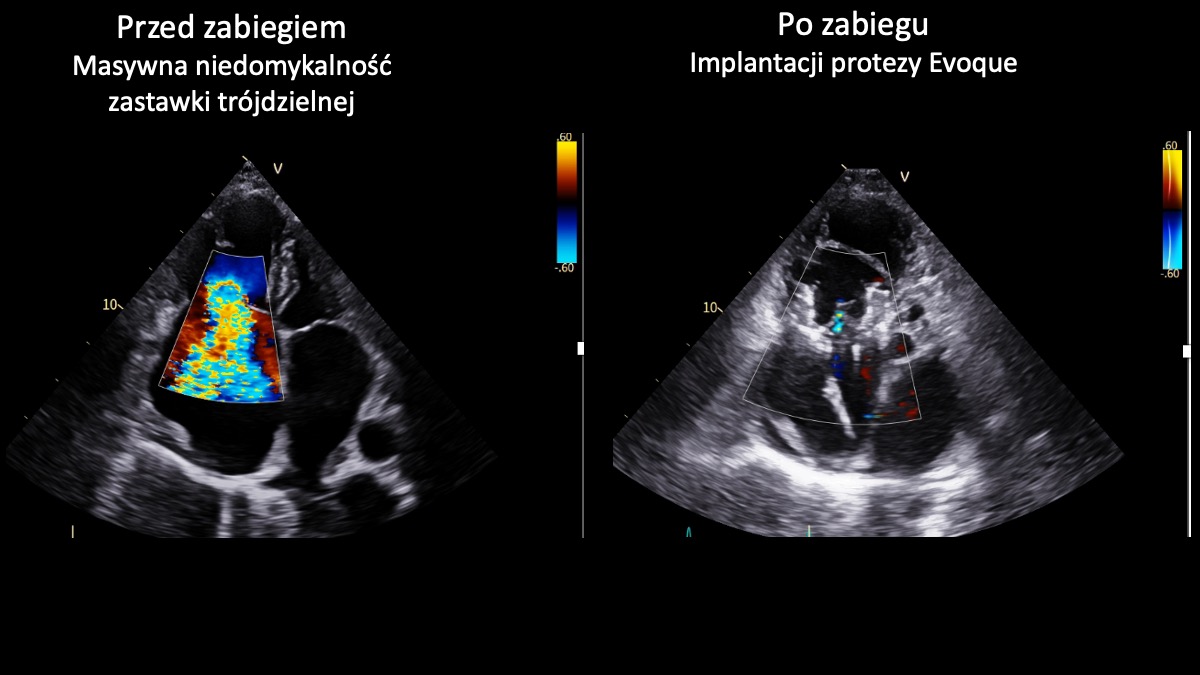

Zespół I Kliniki Kardiologii UCK GUMed, kierowanej przez prof. Marcina Gruchałę, z powodzeniem przeprowadził dwa nowatorskie zabiegi przezcewnikowej implantacji zastawki trójdzielnej Evoque z wykorzystaniem wizualizacji 3D. Te wyjątkowe – także w skali światowej – operacje są odpowiedzią na brak innej terapii dla pacjentów z niewydolnością serca spowodowanej masywną niedomykalnością zastawki trójdzielnej. – Zabiegi tego typu należą do najbardziej zaawansowanych w kardiologii interwencyjnej – podkreśla prof. Fijałkowski.

Zastawka trójdzielna znajduje się w prawej części serca i działa jak „zawór”, który zapewnia prawidłowy przepływ krwi w jednym kierunku. W przypadku niedomykalności nie zamyka się szczelnie, przez co część krwi cofa się, zamiast płynąć dalej. Masywna niedomykalność oznacza bardzo zaawansowaną postać tej wady – cofanie krwi jest znaczne, co prowadzi do przeciążenia serca i objawów takich jak: duszność, szybkie męczenie się czy obrzęki nóg. Nieleczona może prowadzić do poważnego pogorszenia jakości życia i niewydolności serca, a w konsekwencji – do śmierci.

- Obie przeprowadzone implantacje zastawki trójdzielnej Evoque zakończyły się sukcesem. To ważny krok w rozwoju małoinwazyjnego leczenia pacjentów z zaawansowanymi wadami zastawkowymi. Dla chorych obciążonych bardzo wysokim ryzykiem operacyjnym i bez innych realnych możliwości leczenia to obecnie jedyna szansa na skuteczną terapię - podkreśla prof. Marcin Fijałkowski. – Zabiegi tego typu należą nadal do najbardziej zaawansowanych procedur w kardiologii interwencyjnej. Wykonując je w UCK, dołączyliśmy do wąskiego grona ośrodków europejskich oferujących pełne spektrum przezcewnikowego leczenia chorób strukturalnych serca, w tym wad zastawkowych – dodaje.

Zabiegi wykonano u dwóch 80-letnich pacjentek. Pierwszy z nich był monitorowany z wykorzystaniem nowoczesnego systemu echokardiograficznego GE HealthCare Vivid Pioneer, który umożliwia obrazowanie struktur serca w czasie rzeczywistym w technologii 3D. Drugą procedurę wspomagała sonda wewnątrzsercowa Philips VeriSight Pro 3D ICE, pozwalająca na wyjątkowo precyzyjną wizualizację serca podczas zabiegu. Zastosowanie tych technologii czyni przeprowadzone procedury nowatorskimi również w skali światowej. Tego typu zabiegi stanowią przyszłość kardiologii i wyznaczają kierunek dalszego rozwoju leczenia zaawansowanych chorób serca. Obie chore opuściły już szpital w stanie znacznej poprawy.